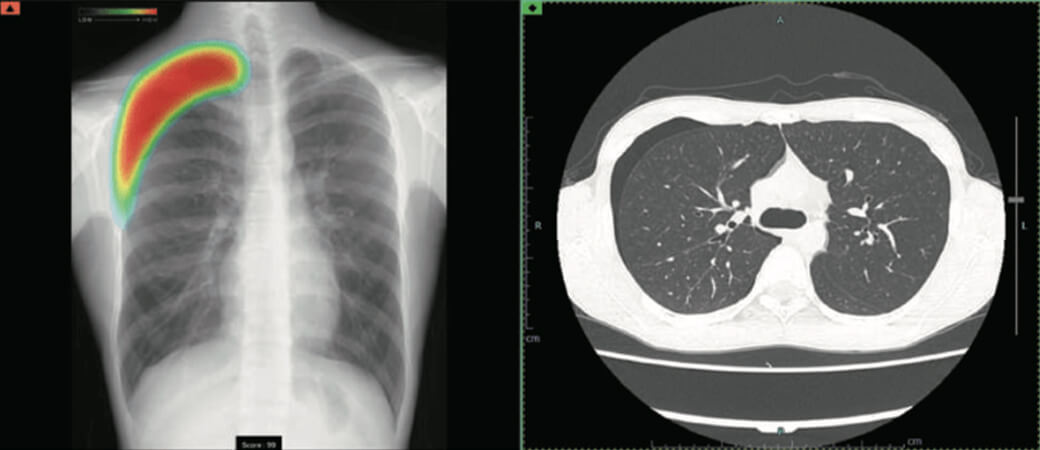

輝い 胸部X線画像診断アトラス 疾患が読める! | 江口研二 吉澤靖之, 医学一般